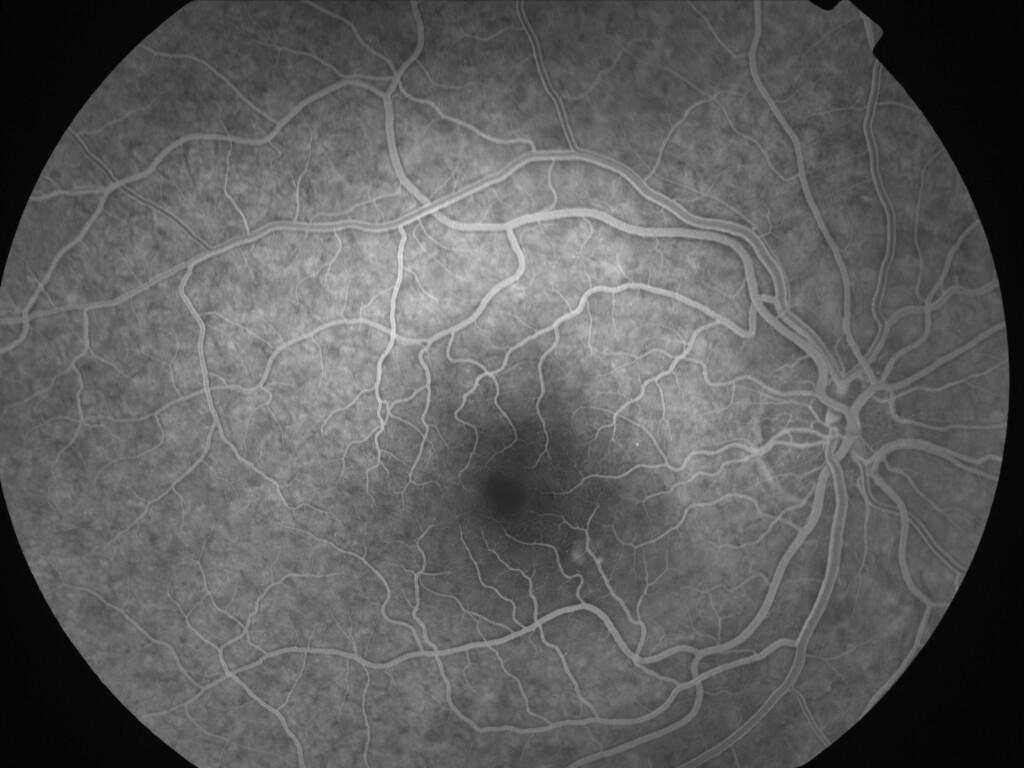

CHORIORETINOPATHIE SEREUSE CENTRALE